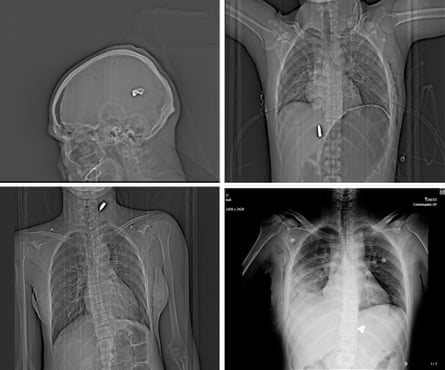

Across the planes of Anahita’s* face, white dots shine like a constellation. Some gleam from inside the sockets of her eyes, others are scattered over the young woman’s chin, forehead, cheekbones. A few float over the dark expanse of her brain.

Each dot represents a metal sphere, about 2-5mm in size, fired from the barrel of a shotgun and revealed by the X-ray camera for a CT scan. Shot from a distance, the projectiles, known as “birdshot”, spray widely, losing some of their momentum. At close range, they can crack bone, blast through the soft tissue of the face, and easily pierce the eyeball’s delicate globe. Anahita, who is in her early 20s, has lost at least one eye, possibly both.

The image of Anahita’s head is one of more than 75 sets of medical images – primarily X-rays and CT scans – shared with the Guardian from one hospital in a major city in Iran, taken over the course of a single evening during the regime’s January crackdown on protesters. The plain, grayscale images tell their own story of the deadly violence inflicted on protesters and onlookers by Iran’s Islamic Revolutionary Guard Corps (IRGC).

They provide further evidence of events described by doctors and protesters across Iran, where guards switched from more traditional ‘crowd control’ to opening fire with high-calibre assault rifles and shotguns. The records present a pattern of people being shot in the face, chest and genitals, a trend also seen in the 2022 “Women, life, freedom” protests. Collectively, they help to illustrate the scale of bloodshed, showing dozens of life-threatening injuries appearing at a single hospital in a midsize city within a few hours.

Many of the images reveal catastrophic injuries that may be fatal even with immediate surgical treatment. The scan of Vahid*, a young man, shows a large-calibre bullet embedded in his neck, his trachea pushed to the right as blood pools and the damaged tissue swells. Scans of another man, middle-aged, show a bullet suspended in his brain, along with a large bubble of gas inside the skull, indicating a devastating brain injury. Medical experts describe it as “likely not survivable”. Two more young men have large-calibre bullets lodged next to their spines. The scan of a young woman shows a deformed bullet that appears to have entered the ribcage under her right arm, torn through the lung, where gas and blood have built up, and come to rest at the left of her spine.

Iran is one of a small number of states where armed forces and police use metal birdshot. While an individual birdshot pellet does not cause as much damage as a bullet, they can still be catastrophic. At long range, when the pellets spray outward, they will hit a crowd indiscriminately. Even a single pellet can cause terrible damage. The X-rays show several cases where just one or two pellets are present in the skull (indicating the person was likely hit at longer range), but they appear to have pierced the eye and come to rest in the socket. At close range, a person may be pierced by hundreds of pellets, causing the destruction of all surrounding soft tissue.

As well as the violence of the injuries, the X-rays are notable for the patterns they reveal: case after case shows patients shot at short to medium range in the face, chest and genitals.

Twenty-nine patients whose records have been viewed by the Guardian have been shot in the face with birdshot. Safie*, a middle-aged woman, still wears simple jewellery in the first CT scan of her head: the thin chain of a necklace dangles against the dark grey of her neck. Also lit up are the metal beads that have burrowed deep into the tissue of her brain. The scans show the progress of medical teams’ efforts to save Safie: a craniotomy, in which a section of the skull is removed either to perform surgery, or to relieve the pressure of the injured, swelling brain crushing against the skull. Later images show that some metal pellets have been removed from the skull, but more than 20 remain embedded in her head and neck. It is not known whether she survived.